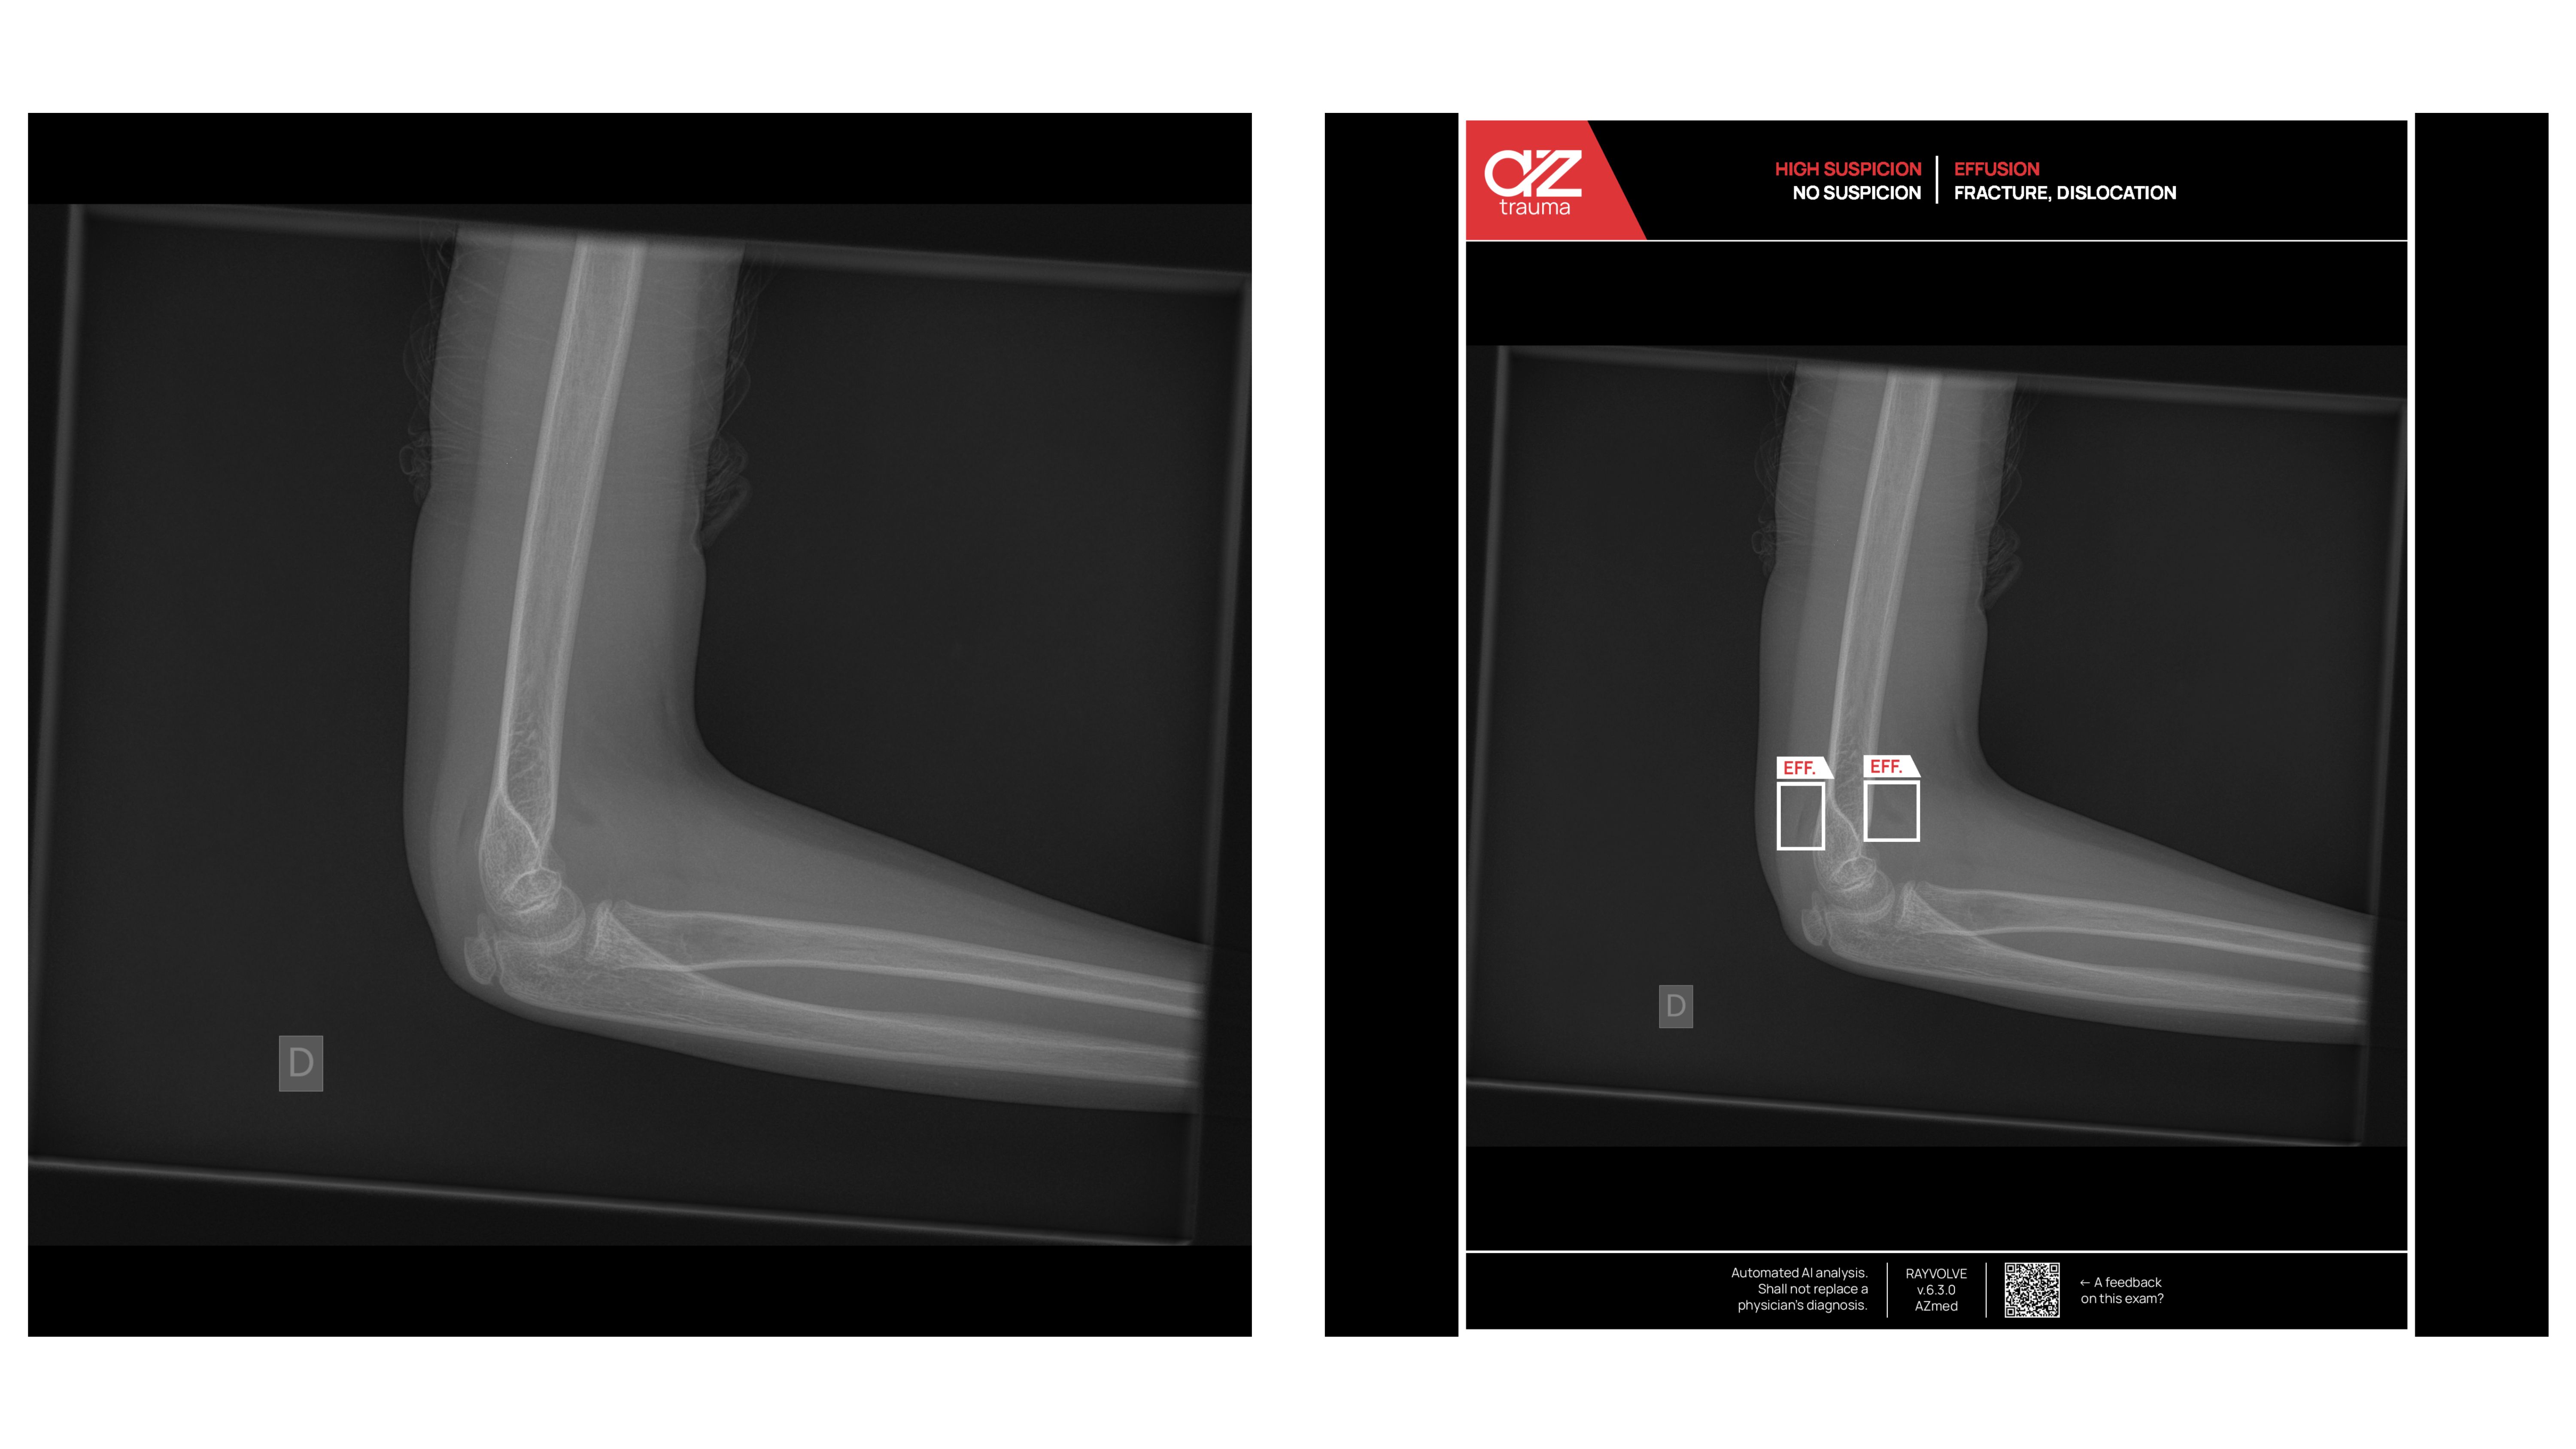

Patient Case 2: Elbow Effusion (Fat Pads)

A single-image elbow X-ray was analyzed with the use of Rayvolve® AZtrauma module, a system for fracture analysis with AI. An increased suspicion of effusion was noted and two regions of interest were highlighted, which were located in the anterior and posterior fat pads. A fat pad sign was visible which indicates the possibility of a primary intra-articular injury that may be commonly linked to occult fractures in the elbow.

The fracture analysis with AI system allowed clinicians to identify indirect signs of trauma associated with a joint effusion pattern and an abnormality that may not have shown on the plain X-ray. When indirect signs are present without a clear fracture, clinicians may complete the evaluation with CT. It is evident that AI has a role in enhancing diagnostic awareness, aiding in the interpretation of the radiograph, and supporting patient management in radiological musculoskeletal imaging.